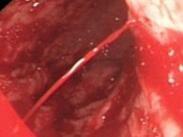

• 上消化道出血

628健康網為您分享有關上消化道出血的癥狀,上消化道出血的治療方法,上消化道出血的預防知識,上消化道出血的癥狀圖片,上...